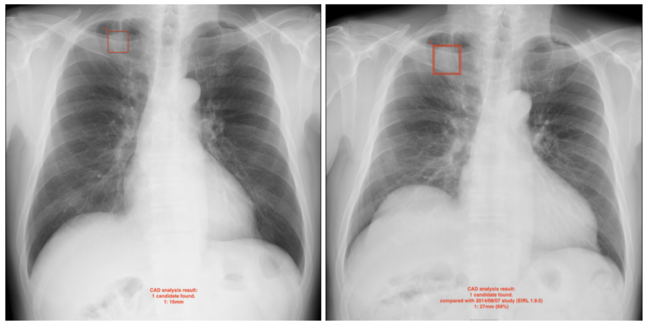

肺結節候補域の経時的変化を検出

新モデルでは,過去に撮影された同一被験者の胸部X線画像と比較し,矩形で抽出された肺結節候補域の経時的変化(増減率)を表示する機能を追加した。(1) 新たな結節影候補域が検出されたケース,(2) 結節影候補域のサイズが増加・減少したケース,(3) 結節影候補域が検出されなくなったケースが表示対象となる。

胸部X線検査で「結節影」が見られた場合,肺がん,肺結核,肺炎などの可能性が疑われる。読影する医師にとっては,過去に実施した検査画像と比較し新たに検出された結節影を一見して分かることが重要である。また,参考指標として肺結節が疑われる領域が拡大していないか経時的変化を観察することがある。

<過去画像(左)と比較して肺結節候補域の増加を示した例>